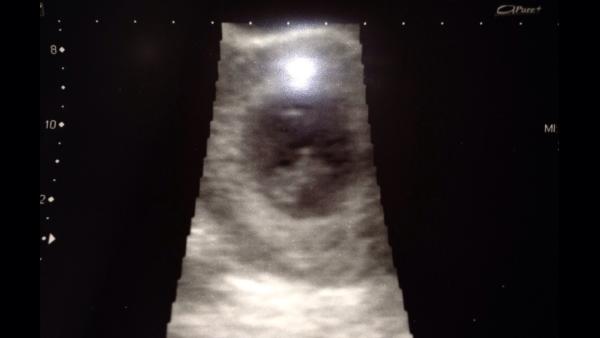

Very special on both sides then Barmy, it'll be fantastic when you tell them!! In case you do decide to get an early scan, I've attached mine to the message (don't think you can see photos on the app though) so you get an idea of what you can expect to see. This was 8+2.

How lovely Bex! Thanks for sharing that, it is lovely to see Smile . I have just shown DH and we have booked an early scan for 7+6 before we go to see his family the next day.

Great about your scan, I'm off that day so will wait patiently to hear all about it!! It's an amazing feeling seeing that little dot on the screen. 12 week one is even more amazing, seeing an almost perfectly forked tiny human!! I'm so excited for you. X